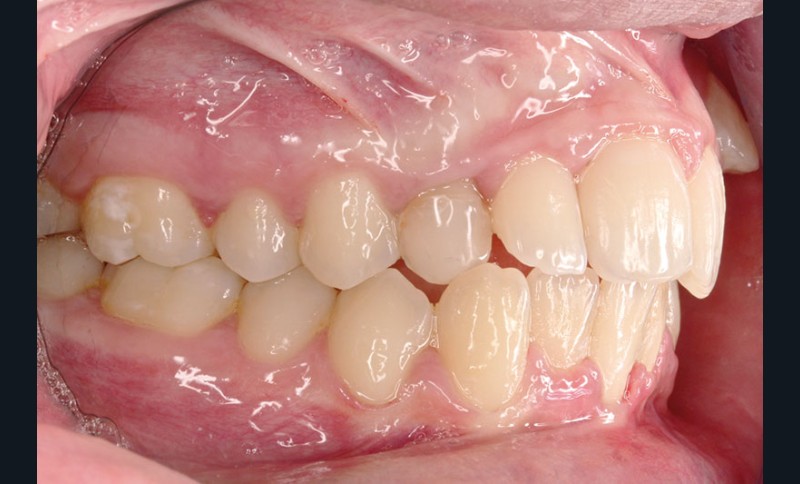

• Endo-buccal : Younesse présente un contrôle de plaque dentaire insuffisant, la persistance de 53 et 63, des soins en cours de réalisation sur 26 et 36, un encombrement maxillo-mandibulaire avec infravestibulotopie de 23 et une suspicion d’inclusion de 13 sur un schéma de Classe II subdivision droite (fig. 3 à 7).

L’examen parodontal révèle une gingivite généralisée ainsi qu’un parodonte très fin et une absence de profondeur vestibulaire.